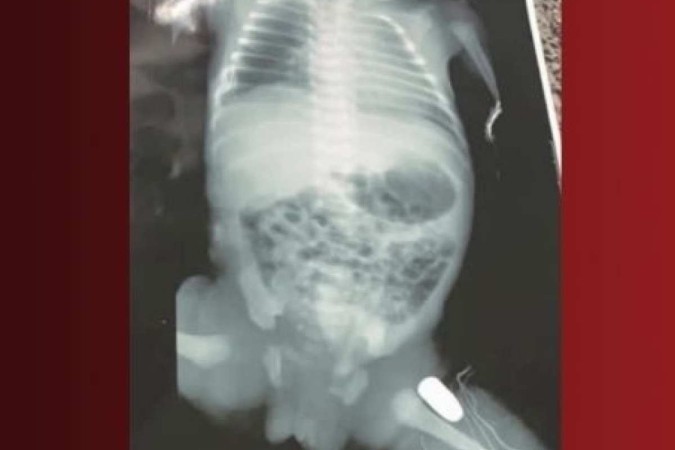

Uma bebê de 32 semanas de gestação foi atingida por um tiro dentro da barriga da mãe, uma adolescente de 16 anos, e sobreviveu. O caso ocorreu na cidade de Imperatriz, no Maranhão. A mãe da criança foi baleada na barriga e teve que fazer uma cesariana de urgência. O projétil ficou alojado na perna do bebê.

A médica e coordenadora da UTI Neonatal da Maternidade de Alto Risco de Imperatriz, Tania Mara Nascimento, disse em entrevista ao G1 Maranhão, que caso a bala tivesse sido alojada um pouco mais acima da perna do bebê, ele poderia ter tido uma hemorragia fatal.

“A cirurgia foi de risco. A localização da bala pelo vasto lateral da coxa esquerda, onde passa estruturas importantes de artérias. Foi uma cirurgia bem complexa, porém foi tranquila, com duração em torno de duas horas. Se a bala tivesse localização mais acima, poderia pegar a artéria femoral, causando uma hemorragia maciça, levando o bebê a óbito’’, afirma a médica.